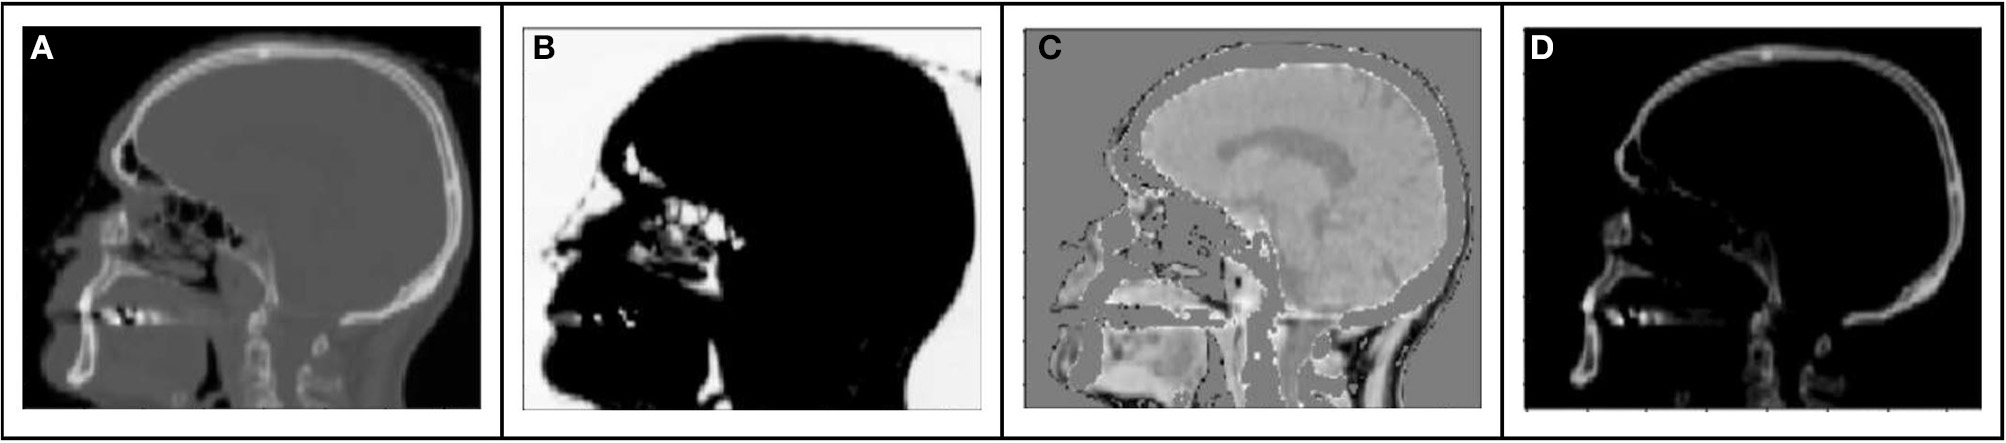

The range of Hounsfield Units of typical human tissues is roughly −1,000 to 2,000. The majority of this intensity range is occupied by air and/or skeletal tissues. Most soft tissue falls within a narrow subset of HU values (~−100 to 100 HU). As a result of this very limited region of the intensity range wherein soft tissue contrast lies, training loss functions will have HU differences an order of magnitude higher in air or bone regions than in locations consisting of primarily soft tissue contrast. As a result, the training might prioritize errors in bone or air over those of soft tissue. This leads to a potential challenge to preserving local soft tissue structures, especially with limited amounts of training data. To attempt to capture soft tissue contrast, we split training CT images into 3 separate output “channels” that can facilitate easier learning from limited data sets (Figure 1). These channels were defined by using intensity thresholds of < −100 HU to define voxels containing air, −100 HU to 100 HU to primarily identify soft tissue and >100 HU for voxels containing bone. The regions outside of the threshold masks were set to 0 HU for each channel. This 3-channel approach forces the network to learn the 3 regions of interests separately, thus capturing the tissue intensity contrasts independently for air, tissue and bone. As the tissue intensities were consistent across the MR scans due to a standard image acquisition methodology and coil configuration, and the HU value ranges of tissues were similarly consistent, a fixed normalization was applied to the input and separately each of the output channels.

FIGURE 1

www.frontiersin.org

Figure 1. Example sagittal CT image with tissue windows: (A) original CT image (B) air window (C) tissue window, (D) bone window.